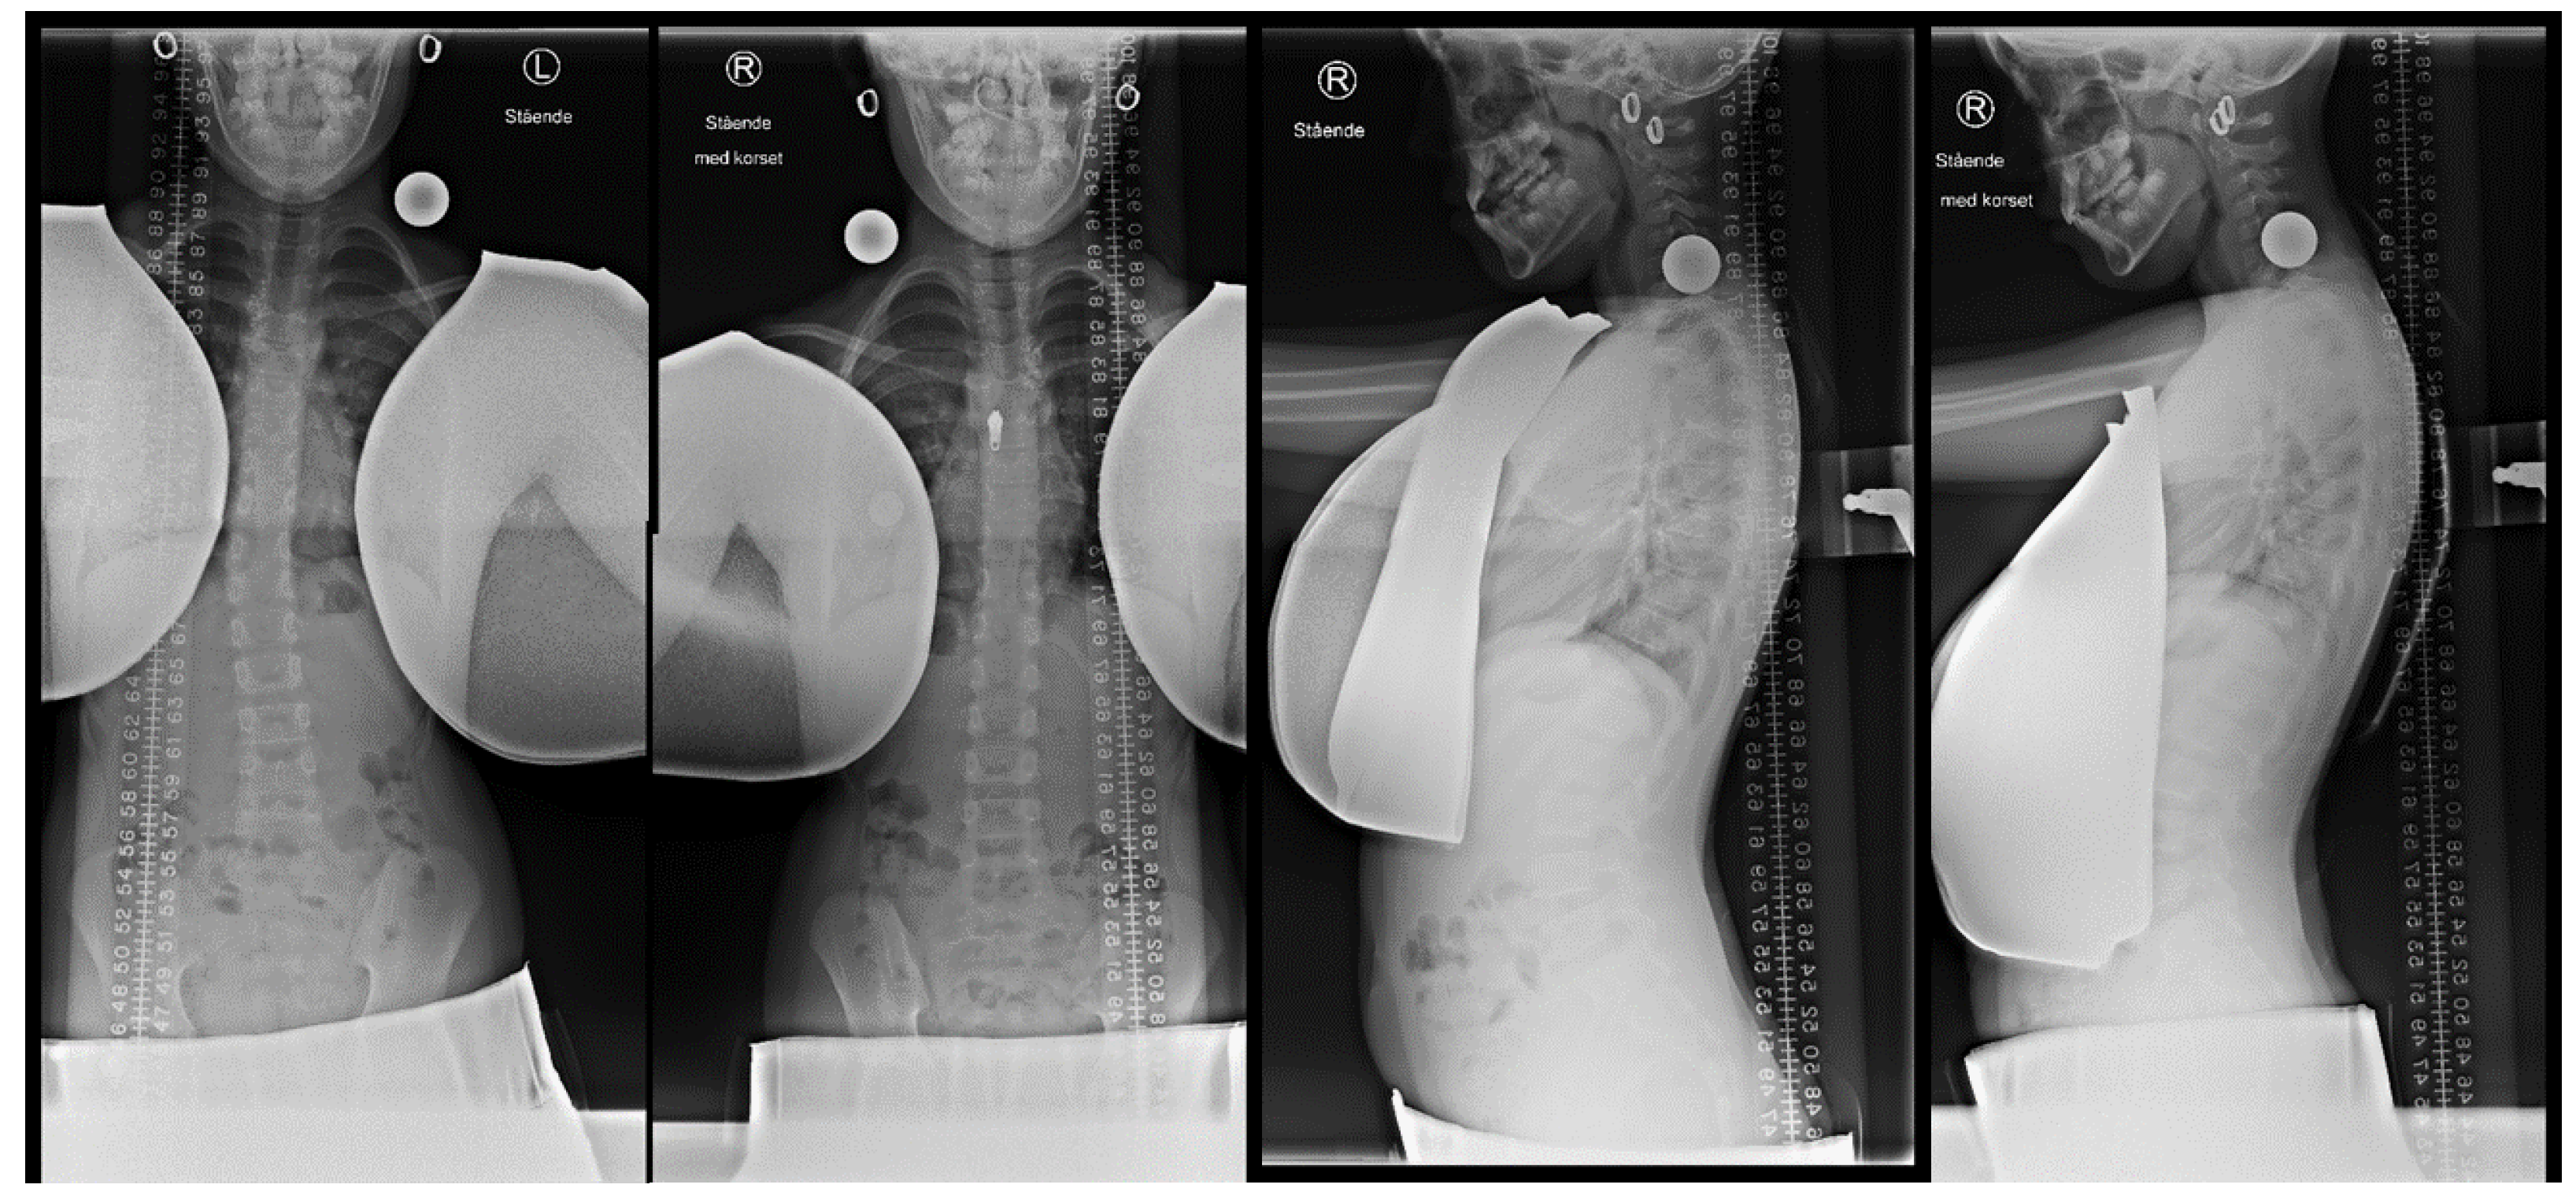

2.2. Initial in-Brace Radiographs